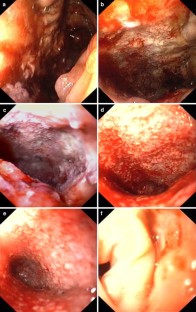

Fig. 1

Fig. 2

Fig. 3